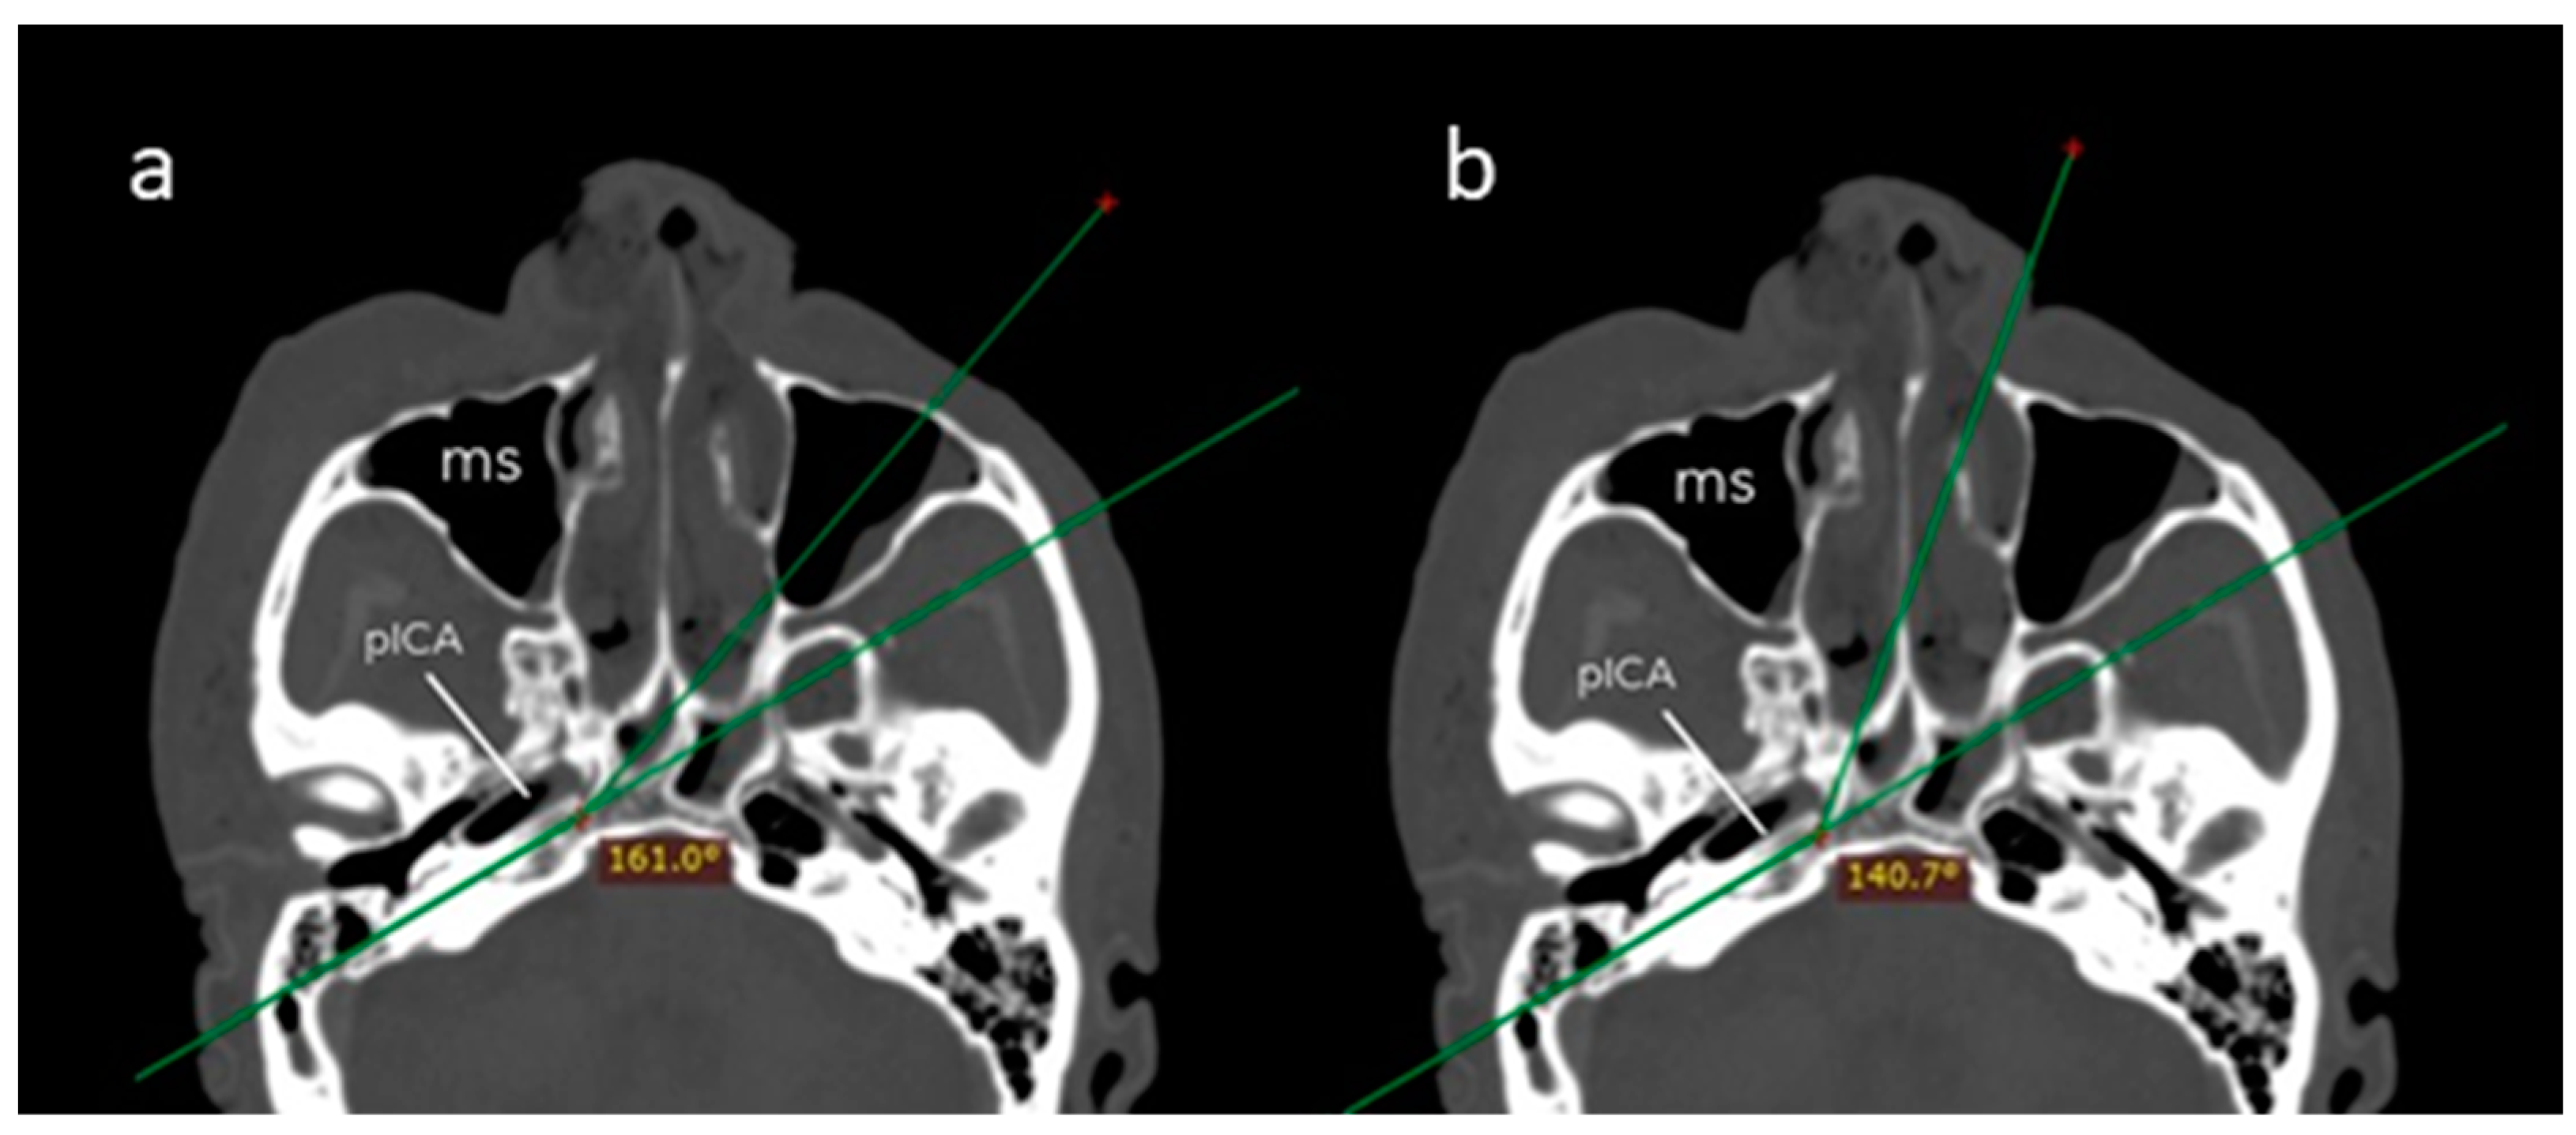

| Transmaxillary Corridor (Mean ± SD) | Endonasal Corridor (Mean ± SD) | p Value | |

|---|---|---|---|

| Angle of attack (°) | 161.1 (8.6) | 140.6 (5.7) | 0.001 |

| Surgical field depth (mm) | 74.3 (4.0) | 88.0 (5.8) | 0.001 |

| Petrous drilling depth (mm) | 17.2 (4.0) | 11.0 (3.3) | 0.008 |